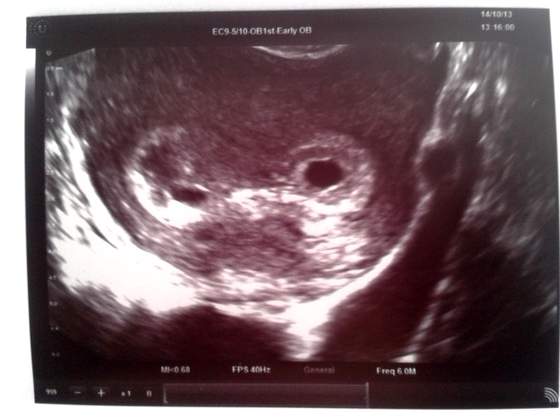

Nie widziałam dziecka, ani serduszka... ale za to widziałam dwa pęcherzyki

Jestem przeszczęśiwa ale i okropnie przerażona... nie wiem dlaczego mam taki mały przyrost bety, lekarz się tym nawet nie przejął, dla niego najważniejsze jest to co widać na USG. Jak się spytałam dlaczego nie widać zarodków to powiedział, że przy ciąży bliźniaczej wszystko się opóźnia, bo hormony dzielą się na dwa i takie tam. W każdym razie kazał mi się nie przejmować. Za tydzień kolejna wizyta i mam nadzieję, że zobaczę dwa bąbelki i dwa serduszka. A lekarz to nawet widział jakiś cień ciania w mniejszym pęcherzyku, ja nie bardzo. A tu moje USG: